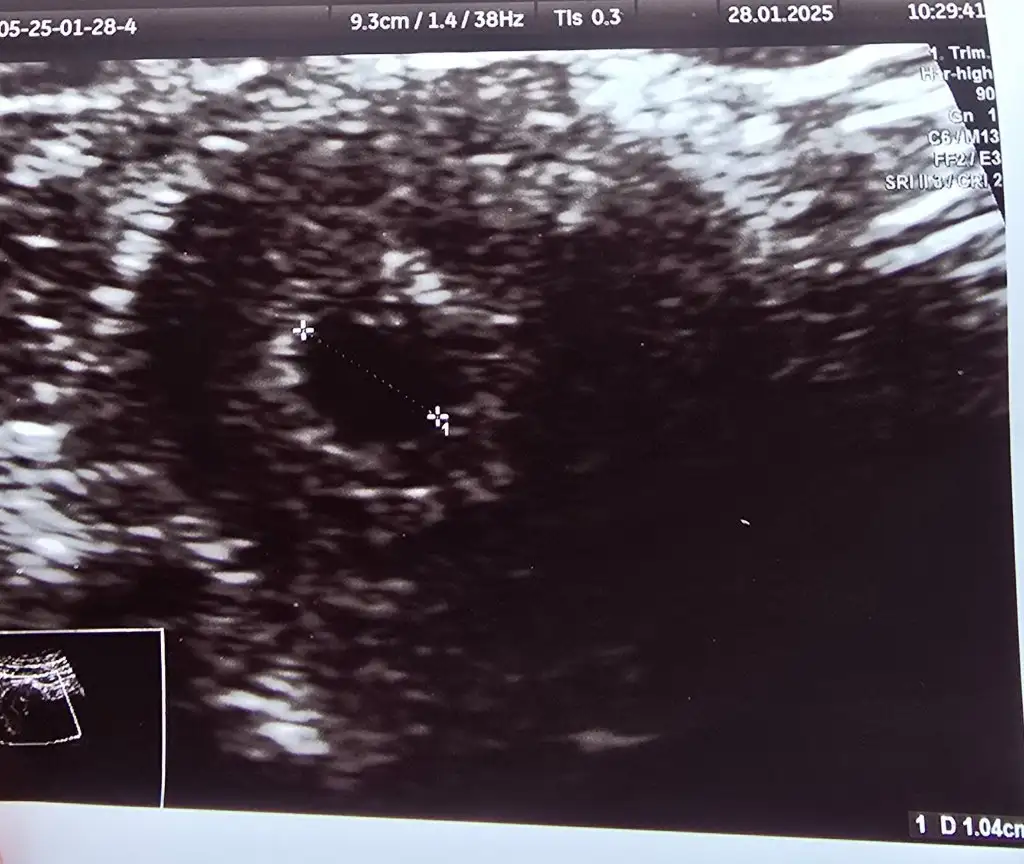

Ayyy maşallah sizin beta kaçken gozuktu kese kese kuzum bide kac haftalik oldu bugun1.04 cm canım

Kese gözüktüğünde beta tahmini 6500 civarıydı 2kat hesapladım 2 g0nde 1Ayyy maşallah sizin beta kaçken gozuktu kese kese kuzum bide kac haftalik oldu bugun

O gün 5 haftalık dedi 1cm kese için (4+6 hesaplamıştım ben ) 1 gün fark oldu